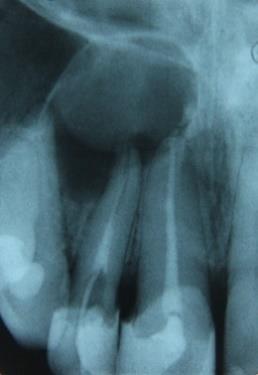

Podane poniżej stwierdzenia przyporządkuj do określonego etapu rozwoju części wierzchołkowej korzenia według Guertsena, przedstawionego na poniższej rycinie: 1) miazga w tym stadium jest tkanką niedojrzałą w związku z tym wykazuje słabą aktywność metaboliczną i niewielkie zdolności obronne; 2) miazga w tym stadium ma dużą aktywność metaboliczną, istnieją wskazania do leczenia pulpopatii odwracalnych metodami przyżyciowymi, a nieodwracalnych - klasycznym leczeniem kanałowym; 3) ostateczne uformowanie korzenia, zakończenie rozwoju zęba oraz tworzenia zębiny i cementu; 4) stadium ścian równoległych, korzeń nie ma jeszcze pełnej długości; 5) stadium ścian zbieżnych, korzeń osiąga pełną długość; 6) w przypadku martwicy miazgi stosuje się klasyczne antyseptyczne leczenie kanałowe ze szczelną ostateczną obturacją kanału; 7) w przypadku leczenia nieodwracalnych zapaleń miazgi stosuje się w zależności od wskazań przyżyciowe lub mortalne metody leczenia endodontycznego; 8) w przypadku martwicy miazgi zachodzi konieczność stymulacji apeksyfikacji; 9) w przypadku leczenia nieodwracalnych zapaleń miazgi metodą z wyboru jest częściowa ekstrypacja przyżyciowa. Prawidłowa odpowiedź to: